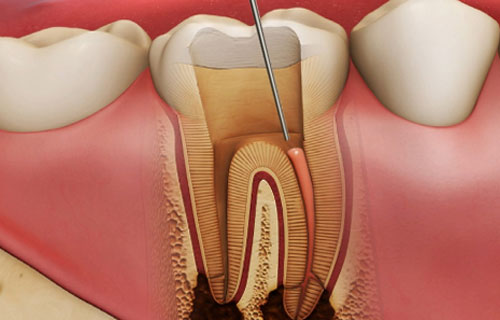

The goal of root canal therapy is to remove bacteria from an infected root canal, prevent the tooth from becoming reinfected, and preserve the natural tooth. In root canal treatment, the inflamed or infected pulp is removed; the inside of the tooth is carefully cleaned and disinfected, then filled and sealed. Modern root canal treatment has nothing to do with the older techniques. Much like a regular filling, usually the treatment completes it in one or two sessions, depending on the condition of individual teeth and needs. Root canal therapy is relatively painless and highly effective. In no time you will be smiling, chewing and biting with ease again. Contact the best root canal treatment in Anna Nagar Chennai!

Root Canal Treatment

Root canal therapy is a process performed to repair and save severely damaged, decayed or infected teeth. A root canal is the process of removing the nerve and pulp, then cleaning and sealing the inside of the tooth. If the above problems are not treated in time, the tissue around the tooth can become severely damaged or infected, resulting in the formation of an abscess. Root canal therapy, also known as RCT, is considered one of the best ways to treat infected teeth painlessly. It is to maintain the success rate of root canal treatment is over 98%.